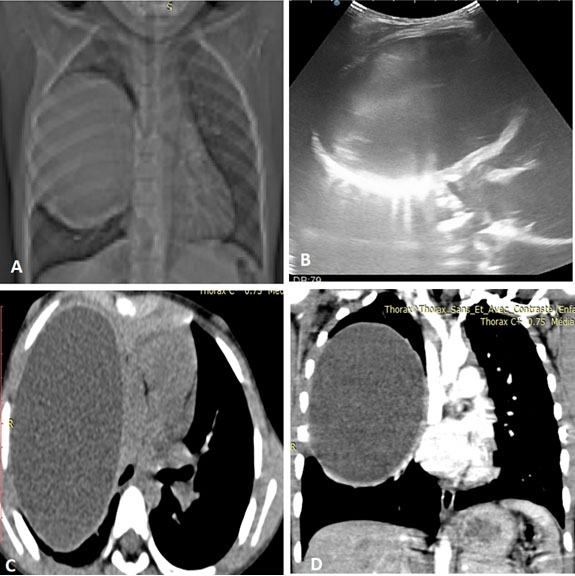

Contrast cranial CT scan showed multiple intracranial ring enhancing lesion bifrontal, right parietal, and occipital sub-dural, right parafalcine ring enhanced hypodense lesion with slight brain midline shift to the left. The patient was commenced on IV antibiotics and antiseizure medication.

She subsequently had right fronto-parieto-temporal craniotomy and ultrasound-guided right occipital abscess aspiration (see Figure 3 and Figure 4). The eloquent areas of the brain were avoided.

Figure 3: Coronal ultrasound image of the similar patient with the abscess cavity (red arrow) seen compressing the lateral ventricle. Associated dilatation of the contralateral ventricle is noted due to hydrocephalus.